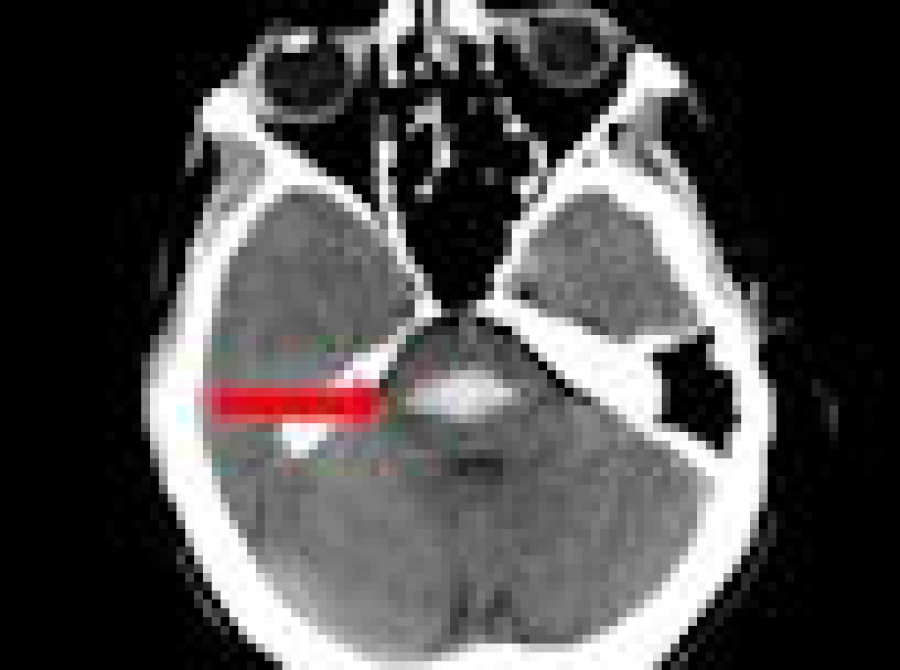

Learn MoreHaemorrhagic Vascular Disease

Haemorrhagic stroke, subarachnoid haemorrhage and vascular anomalies

Learn MoreHead Injury Management

Head injury management, surgery, intensive care and rehabilitation